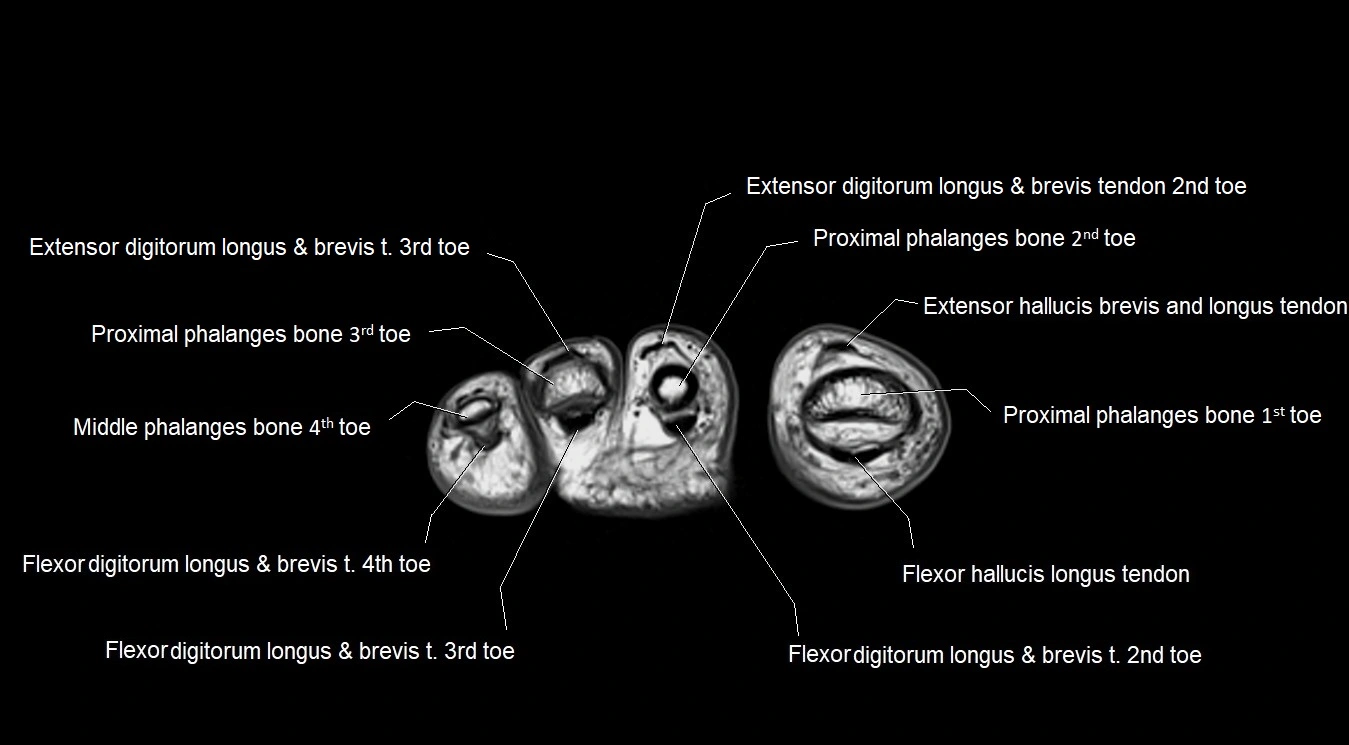

MRI image